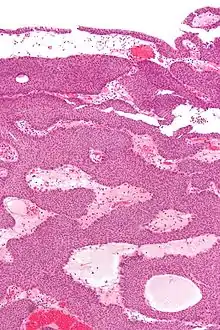

Micrograph of an inverted papilloma of the urinary bladder. H&E stain. | |

An inverted papilloma, also known as Ringertz tumour,[1] is a type of tumor in which surface epithelial cells grow downward into the underlying supportive tissue. It may occur in the nose and/or sinuses or in the urinary tract (bladder, renal pelvis, ureter, urethra). When it occurs in the nose or sinuses, it may cause symptoms similar to those caused by sinusitis, such as nasal congestion. When it occurs in the urinary tract, it may cause blood in the urine.